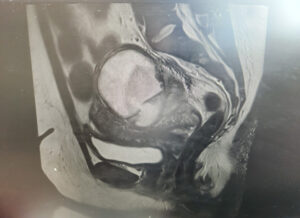

A 32-year-old para 4 woman presented with severe abdominal pain. Laboratory results showed hemoglobin 71 g/L, white cell count 15.4 × 10⁹/L, and C-reactive protein 236 mg/L. She received intravenous co-amoxiclav and metronidazole, along with oral doxycycline.

CT imaging revealed a complex cystic lesion in the pouch of Douglas with involvement of the left ureter and hydroureteronephrosis (Figure 3). MRI confirmed a left TOA with associated iliopsoas myositis and posterior cervical wall invasion (Figure 4). Ultrasound-guided drainage was attempted but was unsuccessful because of adjacent bowel loops. A ureteric stent was inserted, followed by laparoscopic drainage of the abscess (500 mL of pus) and right cystectomy with adhesiolysis. She was tested for tuberculosis and HIV, both of which were negative. She recovered well and was discharged four days postoperatively, with planned ureteric stent removal at follow-up.